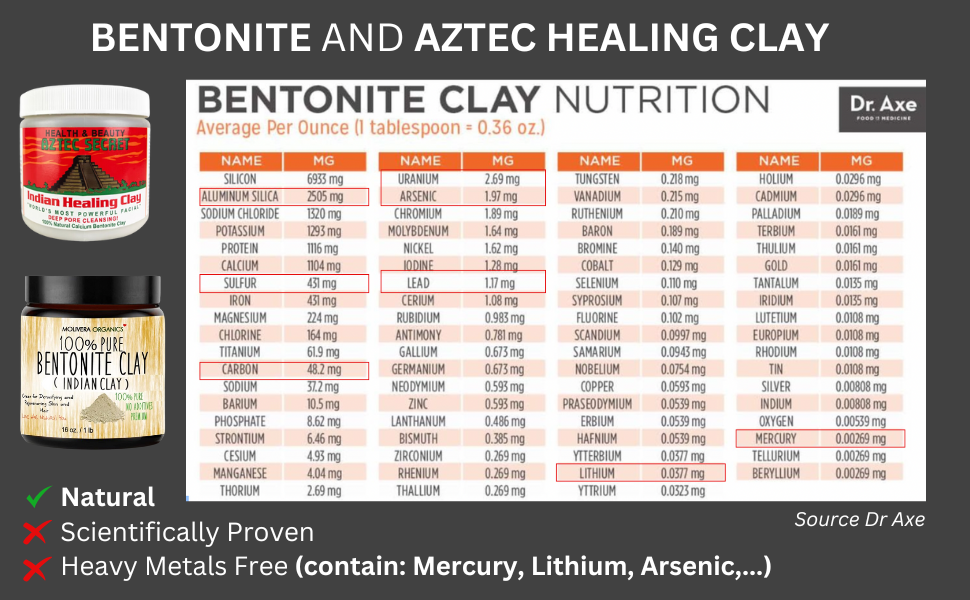

Clayer's French Green Clay represents a fundamentally different approach to sports recovery. Instead of shutting down your body's natural healing processes, it enhances them through mineral-rich therapeutic action.

What makes Clayer different? Our French Green Clay contains over 75 trace minerals that work synergistically to:

- Clayer: CERTIFIED 100% NATURAL, NON-TOXIC, DOPING-FREE

🛡️ COMPLETE SAFETY

- No risk of cold burns or tissue damage

- 100% NATURAL INGREDIENTS

- Safe for extended use